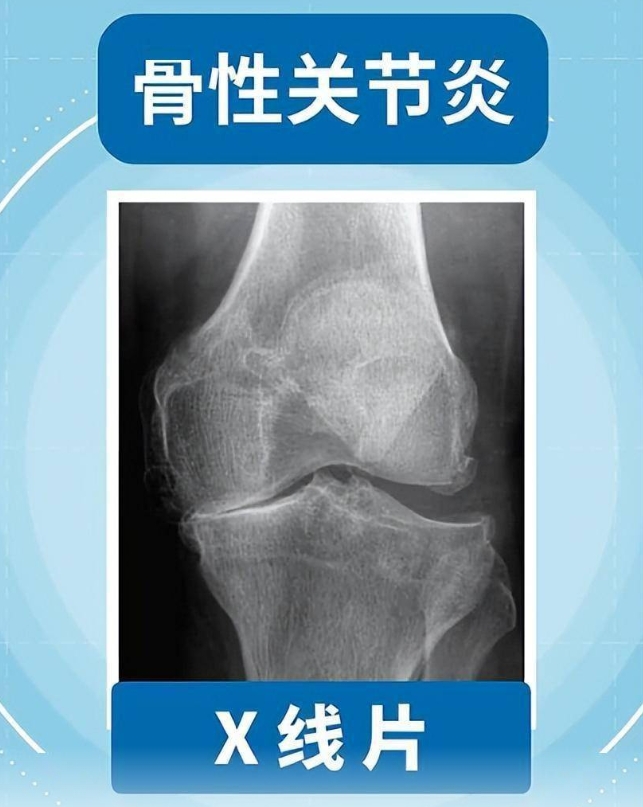

今日头条网页版:且行且珍“膝”!膝盖脆弱的你,请收好这份护“膝”秘籍